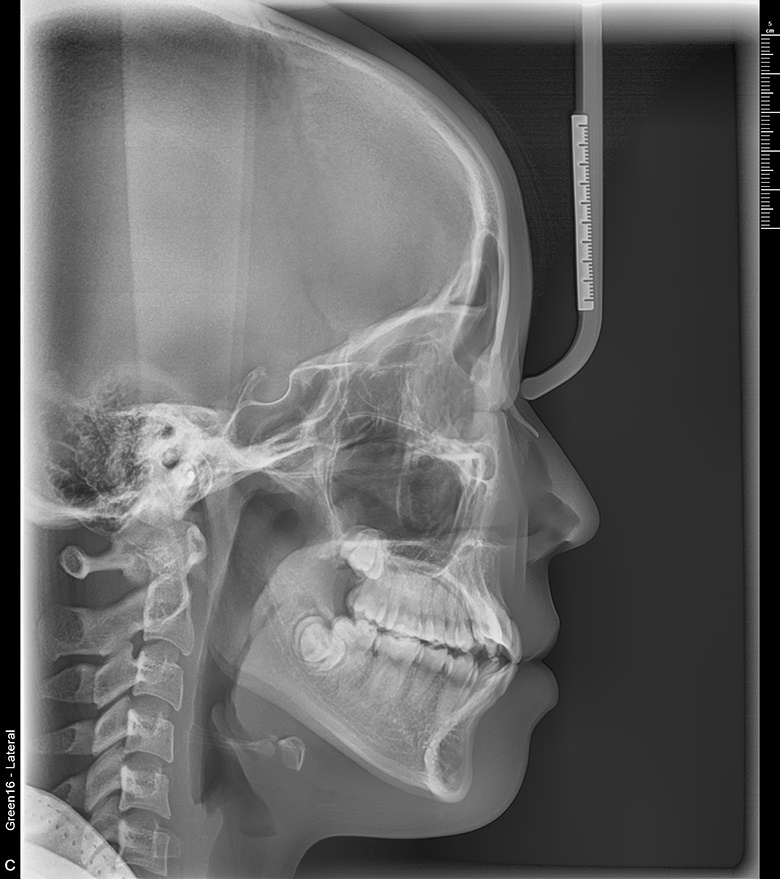

치료 후 사진입니다.